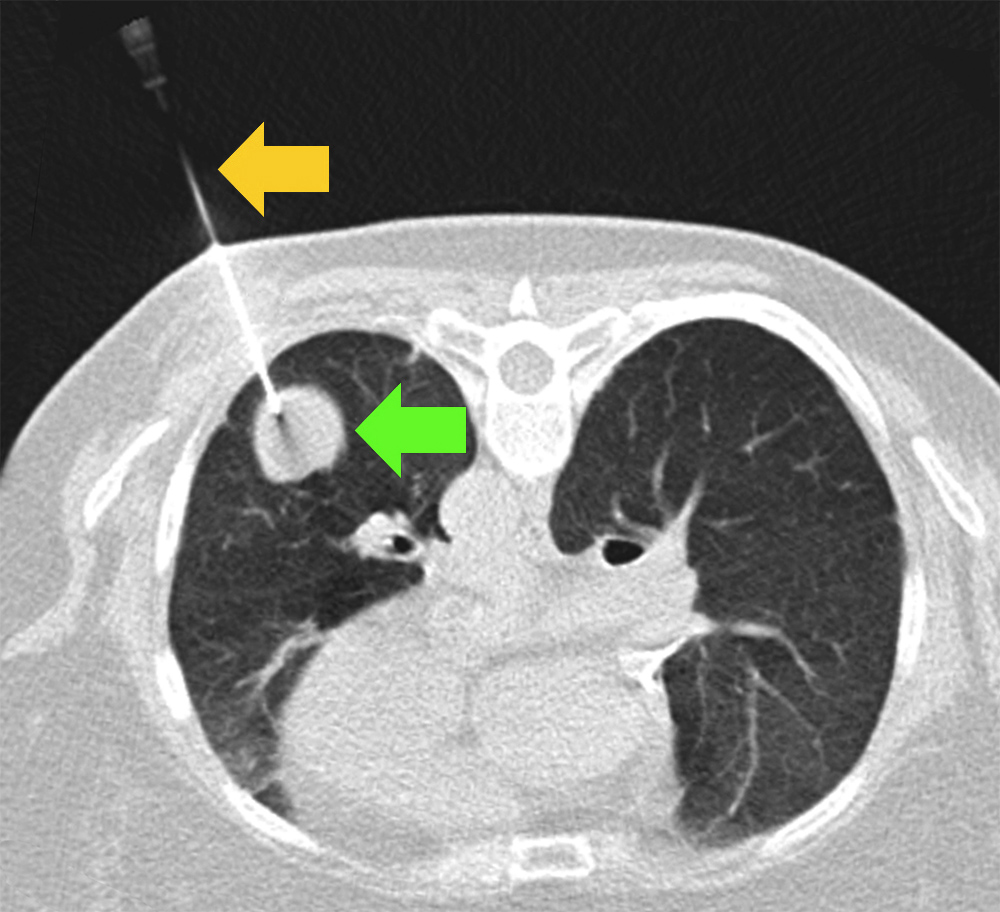

Needle biopsy

A needle guided by a CT scan passes between the ribs into a lung mass. Tissue is evaluated under a microscope.